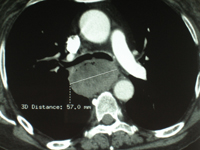

Cancer de l'oesophage